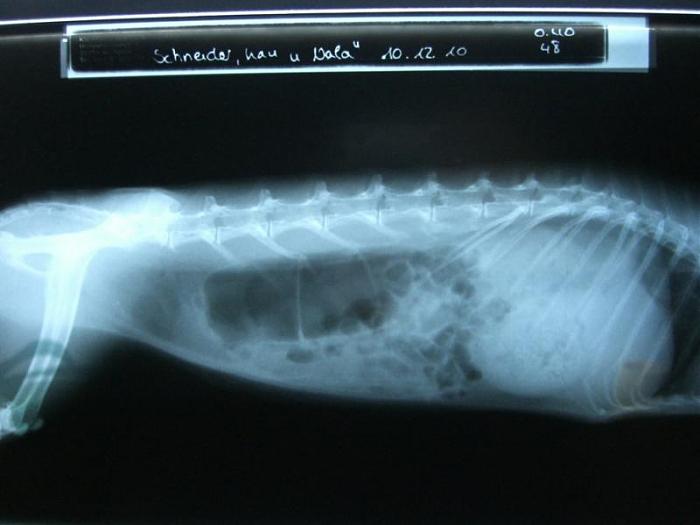

Und sie hat nicht nur mich voll unvorteilhaft geknipst, neeeeeeee sie tut Euch auch noch meinen Kopf von innen zeigen. Ganz schön krumm und schief bin ichNur mein Bauch und mein Herz sieht toll aus